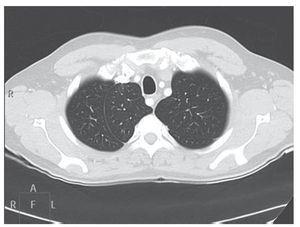

Fístula arteriovenosa pulmonar

Arnalich Jiménez, Ruiz Cobos, Casanova Espinosa, de Santiago Delgado, Hoyos Vázquez

Revista de Patología Respiratoria 2012;15:33-5